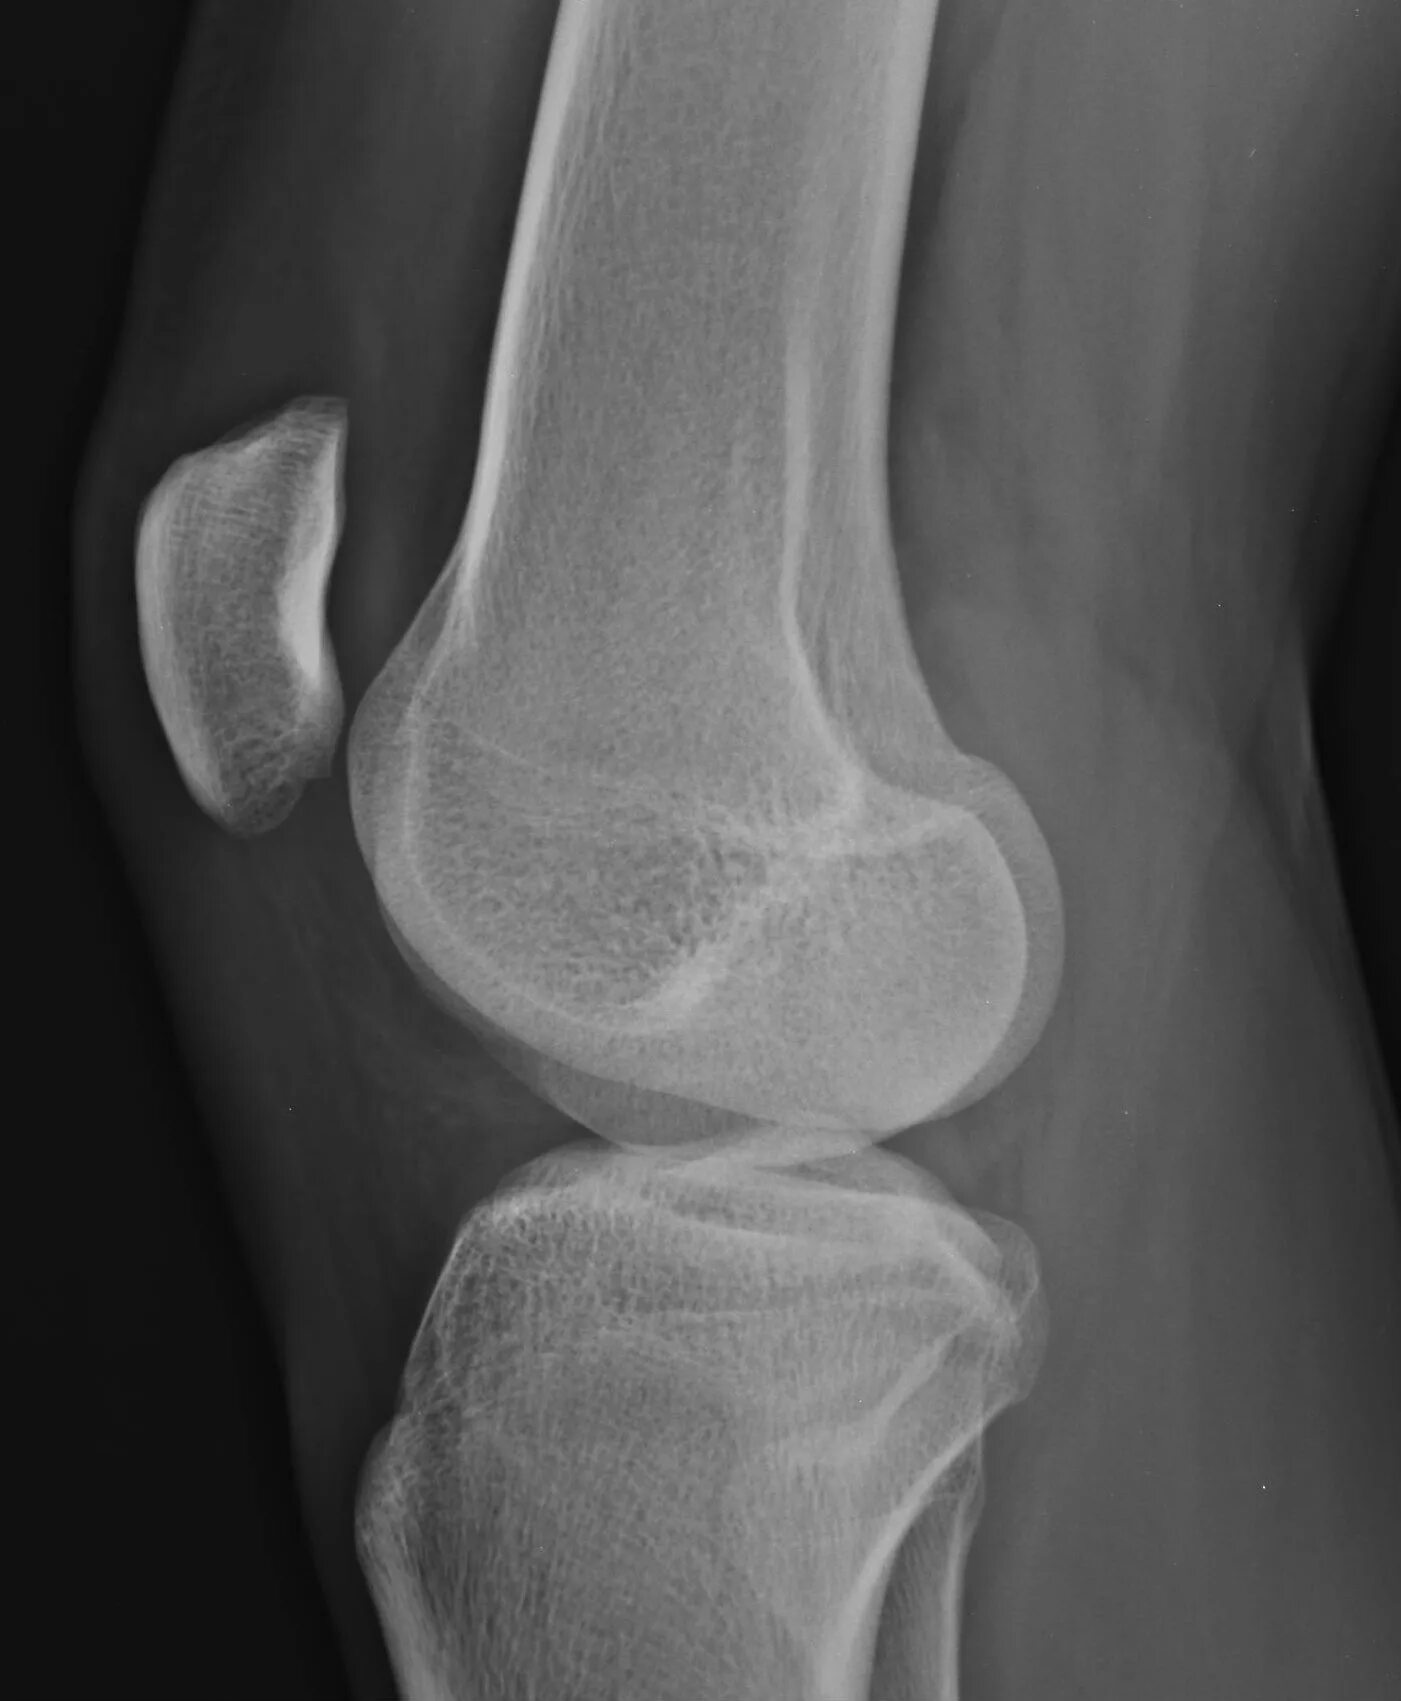

Болезнь шляттера код по мкб